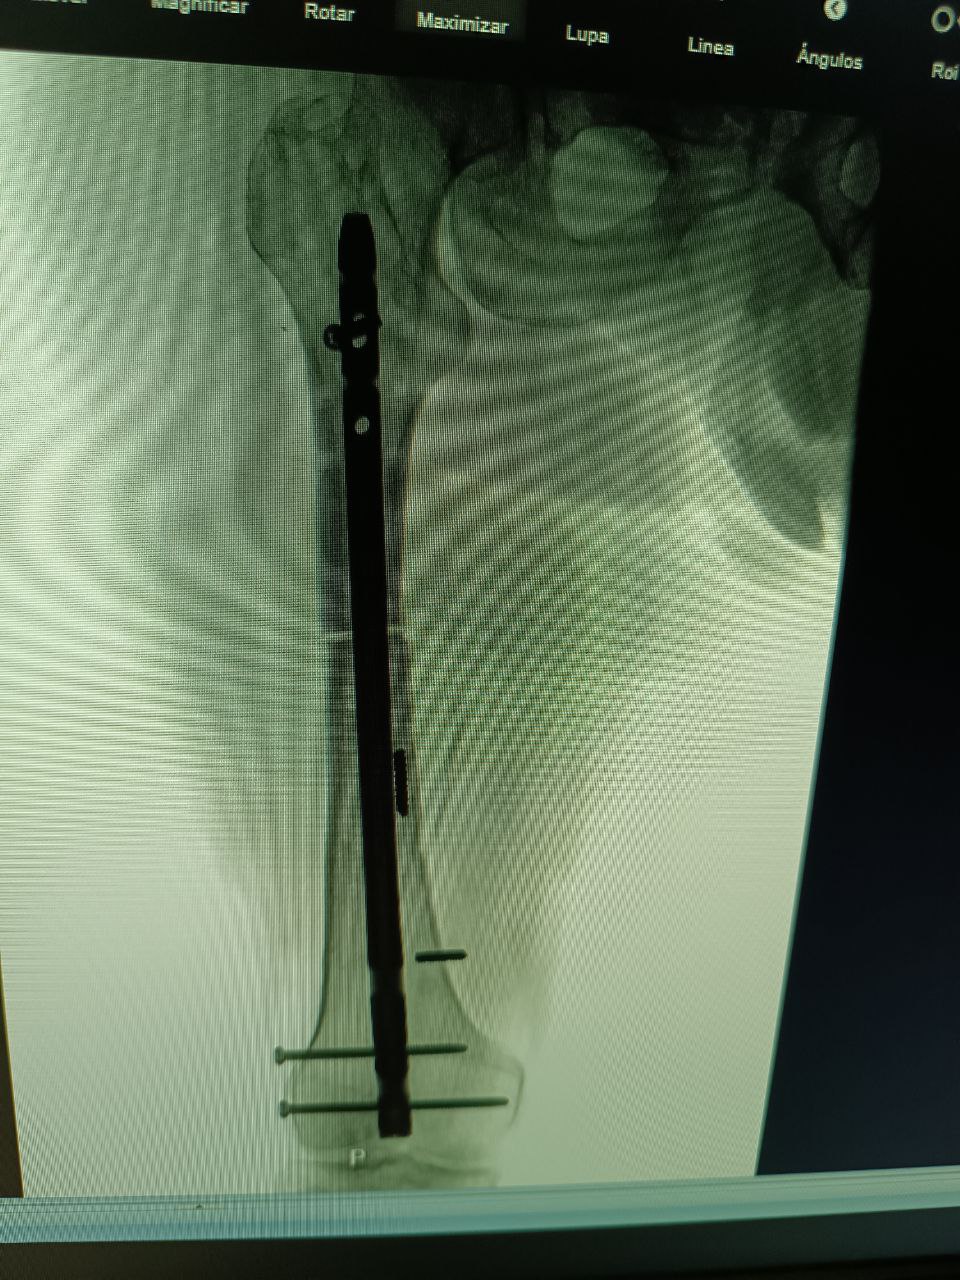

Osteosíntesis Compleja

Fijación interna avanzada con placas, tornillos y clavos para el tratamiento de fracturas que requieren estabilización quirúrgica de precisión.

- Placas y tornillos LCP

- Clavos intramedulares

- Fijación percutánea

Cirugía Reconstructiva

Recuperación exitosa tras cirugía de alta complejidad

Osteosíntesis Compleja

Fijación interna con placas y tornillos de precisión

Alargamiento Óseo con Clavo Endomedular

Corrección de deformidades y transporte óseo

“Tras un accidente con fractura de fémur, el Dr. Vásquez me realizó una osteosíntesis con placa LCP. La recuperación fue mucho más rápida de lo esperado. Muy profesional y atento en todo momento.”

Ricardo Torres

Osteosíntesis de Fémur